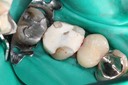

Gary Umeda #3 - 4 prep